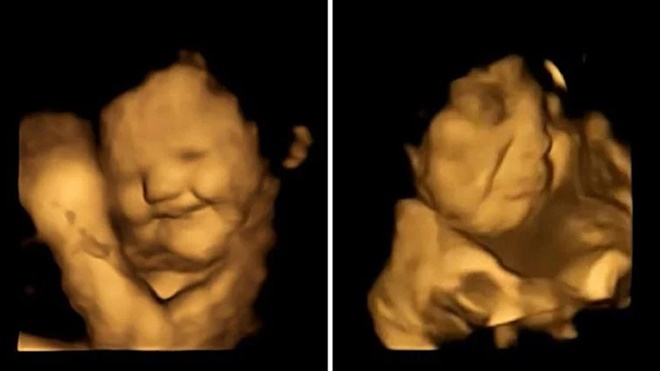

Anne karnındaki bebekler şaşırttı